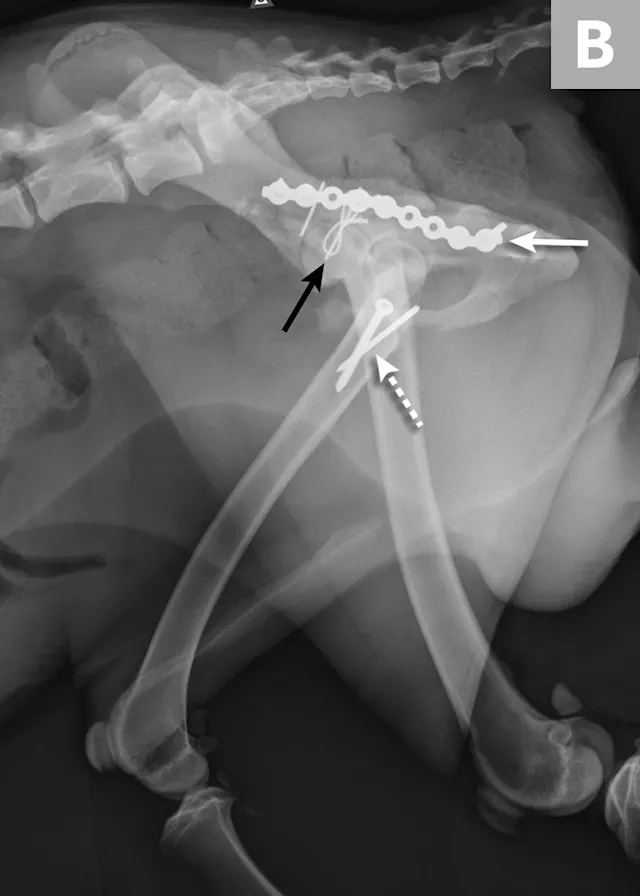

FIGURE 4A

Postoperative ventrodorsal (A) and lateral (B) projection images of the same dog in Figure 2. Fracture reduction was achieved with cross pins and a figure-eight hemicerclage wire (black arrows). Reduction was protected via application of a locking string-of-pearls neutralization plate (solid white arrows). To gain access to the full extent of the fracture, a greater trochanteric osteotomy was performed and stabilized with a positional screw and pin (dashed arrows). The ventrodorsal postoperative radiograph revealed a sacral fracture not previously appreciated (arrowhead). The fracture was successfully treated with conservative management.